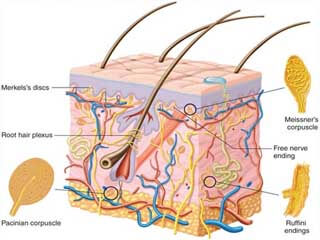

قیمت: 156٬000 تومان - دسته بندی فایل: پاورپوینتپاورپوینت آناتومی و فیزیولوژی پوست

فروش ویژه پاورپوینت حرفه ای آناتومی و فیزیولوژی پوست باتخفیف استثنایی فقط 84000هزارتومان تعداداسلاید.117اسلایدکامل